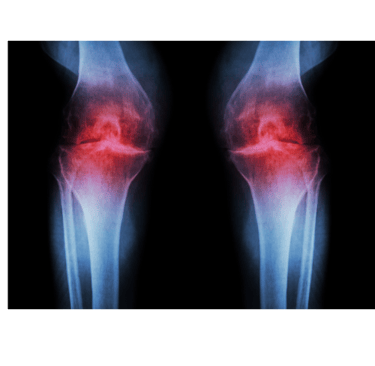

Es la destrucción progresiva del cartílago articular provocada por una interacción de factores de riesgo, estrés mecánico (sobrecarga) y mecánica articular alterada.

Esto genera inicialmente una inflamación articular (mediante marcadores proinflamatorios y proteasas) y finalmente se produce una destrucción del cartílago.

De forma temprana se desarrolla fibrilación superficial, irregularidad y erosiones focales. Estas erosiones eventualmente se extienden hasta el hueso y se expanden continuamente para involucrar una mayor parte de la superficie articular.

Con el tiempo, la matriz de colágeno (proteína del tejido) se daña, los condrocitos (células del cartílago) proliferan y se forman condrocitos hipertróficos, lo que provoca crecimientos anormal de cartílago que se osifican y forman osteofitos (protuberancias óseas). También se genera una inflamación sinovial que puede afectar a tejidos blandos de alrededor: cápsula, ligamentos y meniscos.

Cabe remarcar que NO todas las personas que presentan signos de artrosis en imágenes complementarias (radiografías) tienen porqué presentar síntomas. La degeneración articular es un proceso fisiológico progresivo que se da con la edad. Solo se le ha de dar importancia cuando las imágenes pueden correlacionarse con la clínica.